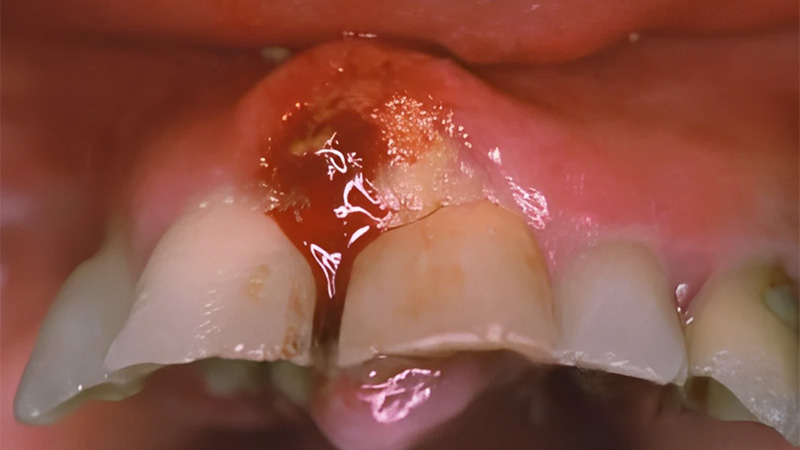

Fig. 01 : tumeur ulcéro-bourgeonnante de la lèvre inférieure.

Cancer du plancher buccal

Le cancer du plancher buccal représente 15 à 20 % des cancers de la cavité buccale.

Anatomie pathologie : dans 90 % des cas, ce sont des carcinomes épidermoïdes. Les facteurs étiologiques sont essentiellement le tabac et l’alcool.

Fig. 02 : tumeur du plancher antérieur gauche.